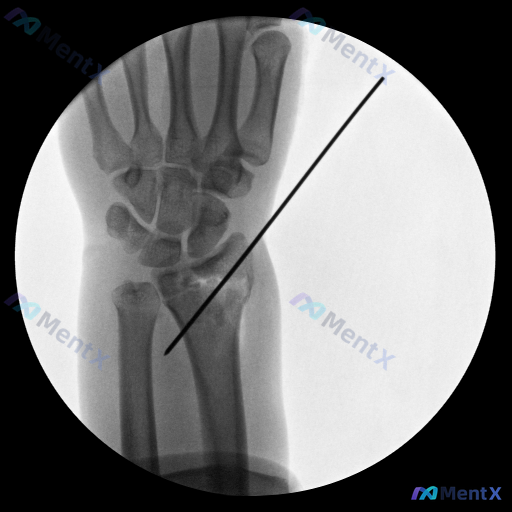

整理到一个腕关节术后的影像病例资料,大家看看这种情况第一反应会往哪边考虑? 基本情况: - 腕关节正位X光片(术后复查背景) 影像客观表现: 1. 腕骨排列尚可,无明显腕骨间脱位/半脱位;尺骨茎突未见明确骨折线;下尺桡关节对合可 2. 桡骨远端可见明显骨质破坏区,骨质密度不均匀(透亮区与密度增高区交...